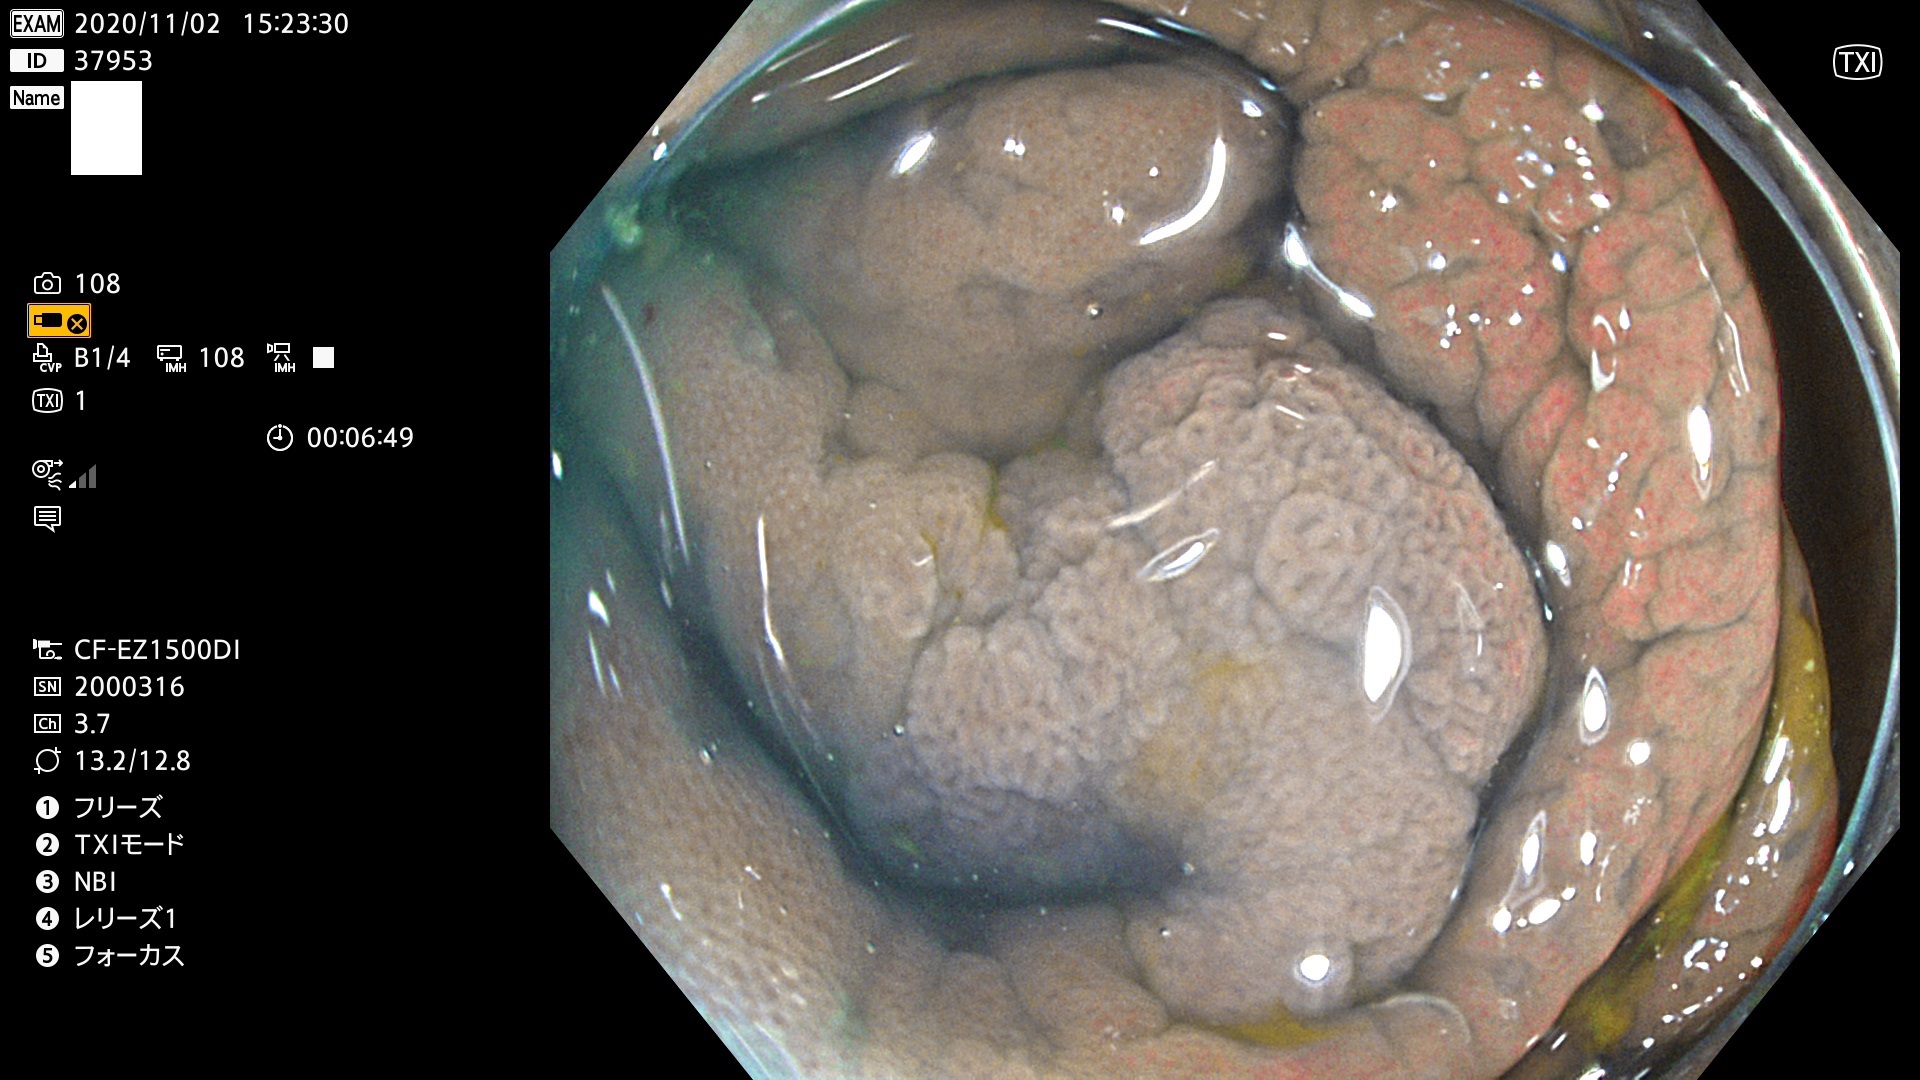

37900 37902 37903 37904 37905 37906 37907 37909 37910 37911 37912 37913 37914 37915 37916 37917 37919 37921 37922 37923 37926 37928 37929 37930 37931 37933 37934 37935 37936 37937 37938(SSAPのみ) 37939 37940 37941 37942 37943 37946 37947 37948 37949 37951 37952 37953(SSAPのみ) 37955 37956 37957(SSAPのみ) 37958(SSAPのみ) 37960 37962 37963 37964 37966 37967 37968 37971 37972 37973 37975 37976 37977 37979 37982 37983 37984 37985 37986 37987 37988 37989 37990 37991 37992 37993 37994 37995 37996 37998 37999

発見困難で危険性の高い平坦型病変(上記100名より抽出)